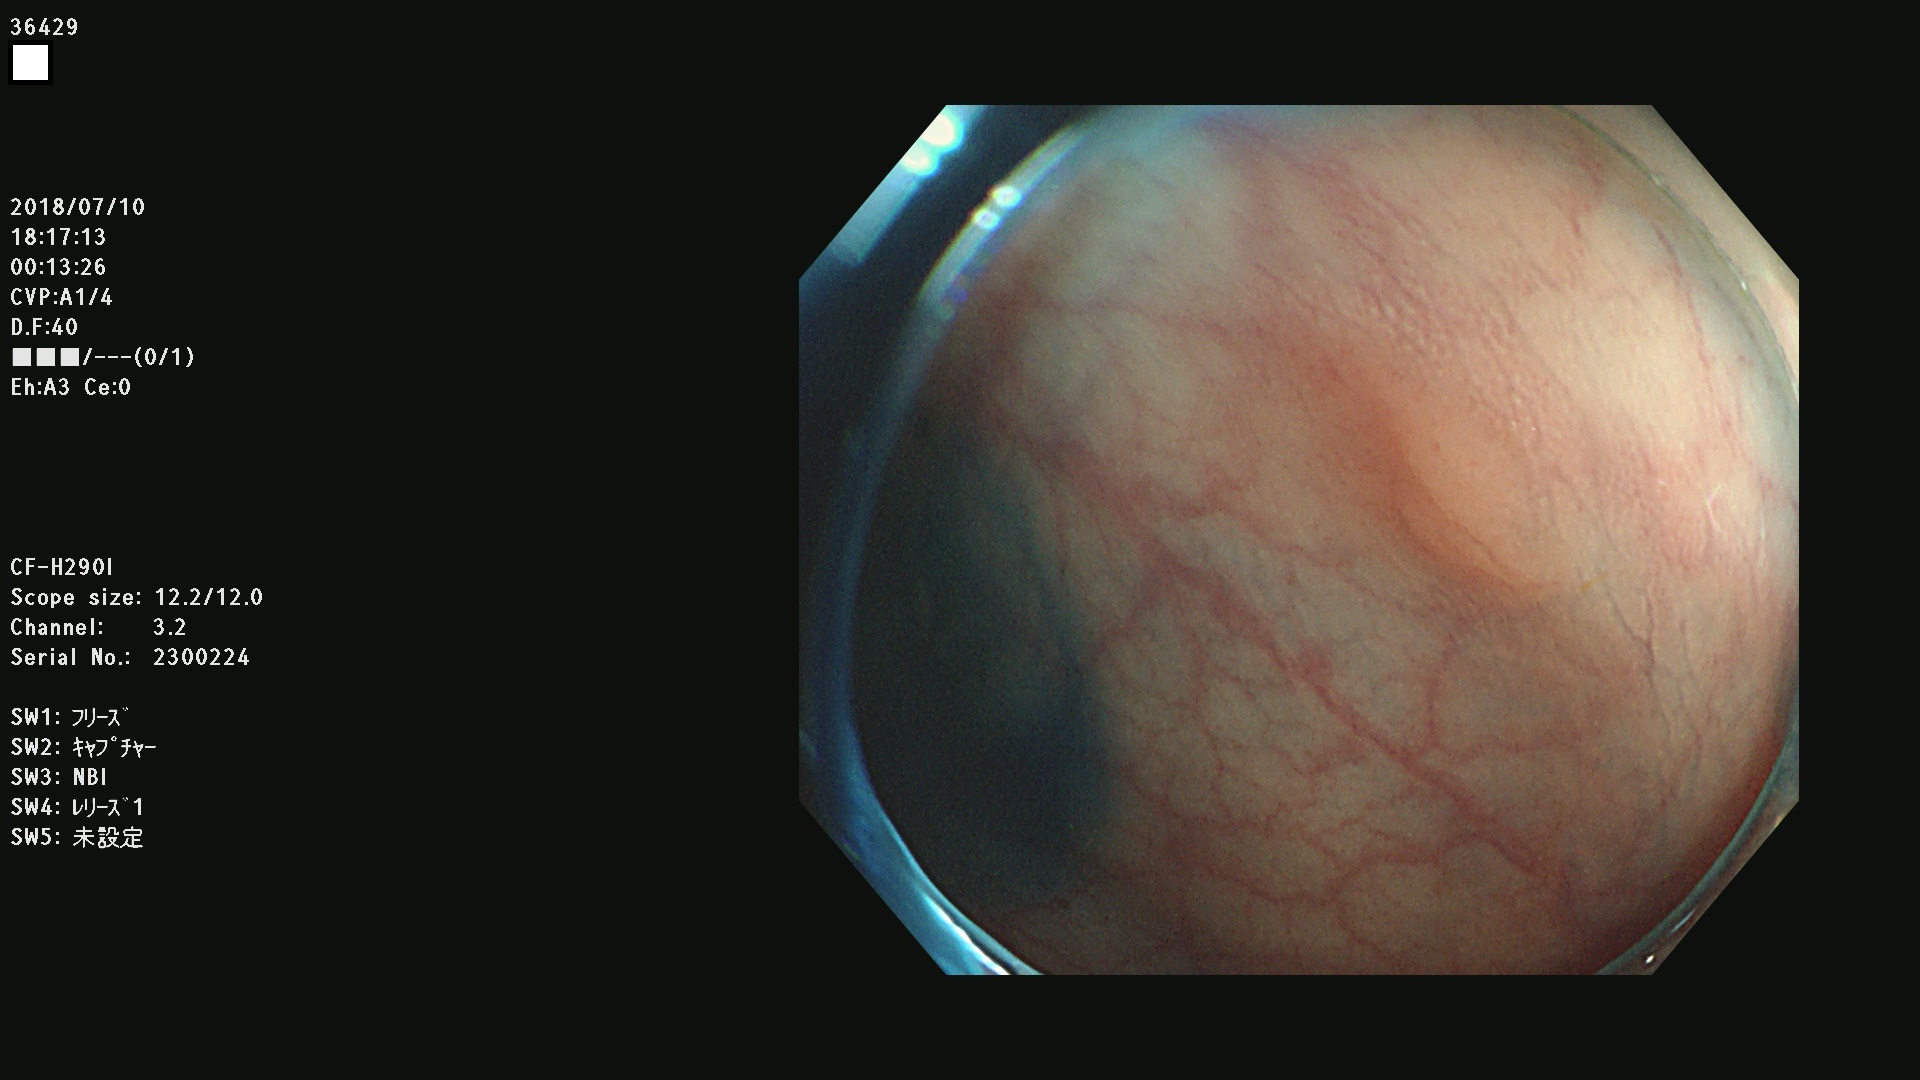

36400(SSAPのみ) 36402 36403 36404 36405 36406 36407 36408(SSAPのみ) 36412 36413 36414 36415 36416 36417 36418 36420 36422 36423 36424 36425 36426 36428 36429 36430 36431 36434 36435 36436 36437 36438 36440 36443 36447 36448 36449 36450 36452 36454 36458 36459 36460 36462(SSAPのみ) 36463 36464 36465 36466 36470 36471 36472 36473 36474 36475 36476 36478 36480 36481 36482 36484 36487 36488 36489 36490 36492 36494 36495 36496 36497 36498

発見困難で危険性の高い平坦型病変(上記100名より抽出)